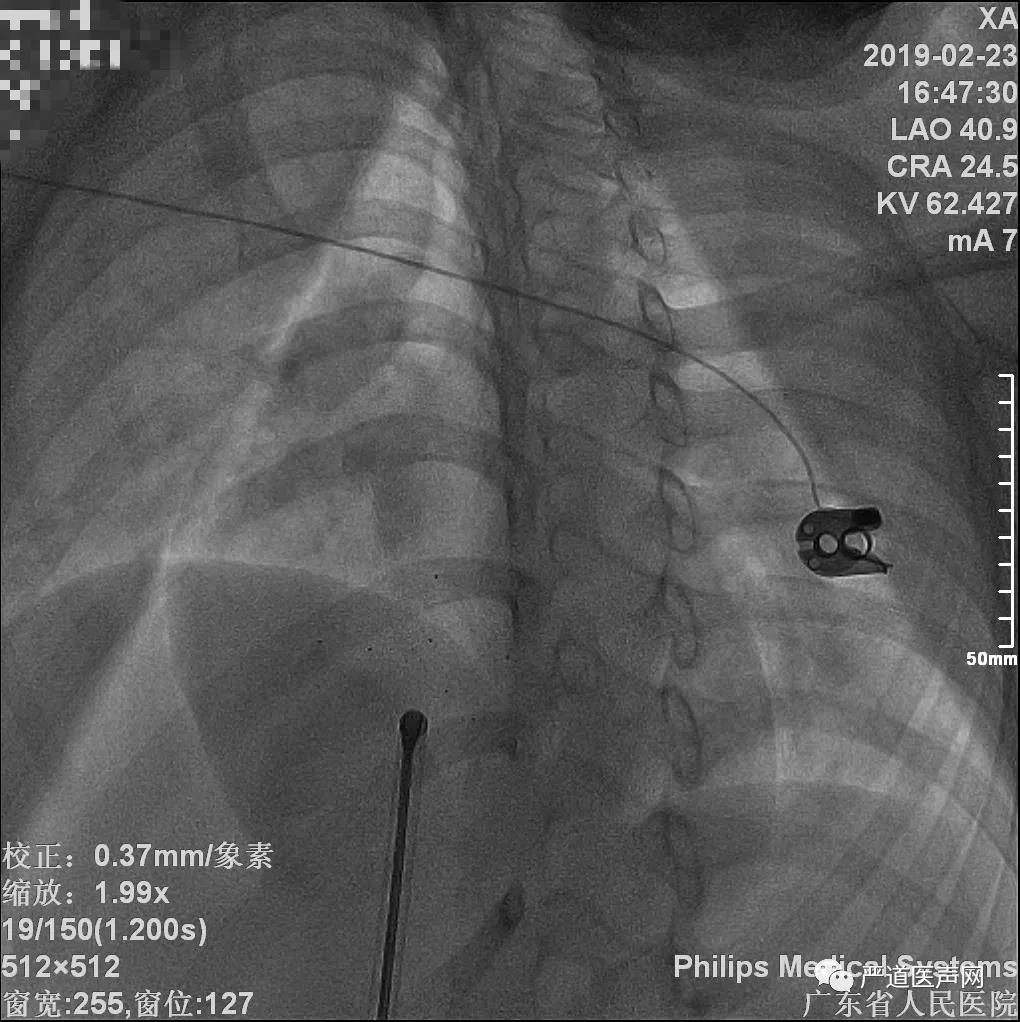

选择10F输送鞘管,输送至左心房,退出扩张条及导丝,将可吸收封堵器(LifeTech Absnow,18mm)系统沿鞘管输送至左上肺静脉,在左前斜45°,头位20°透视及超声心动图引导下,逐步释放封堵器,后撤鞘管,使封堵器的封头(1个显影点),左侧伞盘(2个显影点),腰部(2个显影点),及右伞盘(2个显影点)逐步释放,左侧伞盘释放后采用超声引导,确保伞盘紧贴房间隔左房面,释放封堵器后操纵控制手柄,锁定伞盘。

术后造影显示可吸收封堵器特点,可见其X线显影点

同时,为了方便X-Ray下的观察,在封堵器两侧的PLLA伞盘上,各设计了数个X线显影点,用以帮助介入操作。